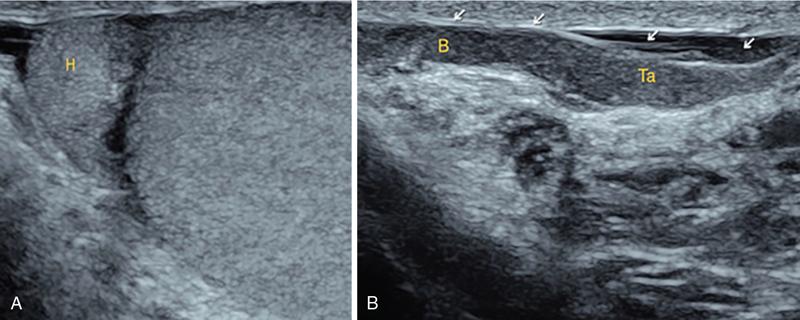

IMAGING ANATOMY OF MALE REPRODUCTIVE SYSTEM Ganesh Rajagopal The male reproductive system is formed by testes, ejaculatory ducts, seminal vesicles (SVs), prostate and penis. Various diagnostic imaging modalities like ultrasound (US), computed tomography (CT), magnetic resonance imaging (MRI) and positron emission tomography (PET) are helpful in the diagnostic evaluation of male reproductive system. Various indications for imaging may include acute scrotum (testicular torsion, trauma and epididymo-orchitis), scrotal swelling (hydrocele, spermatocele, idiopathic scrotal wall oedema and scrotal abscess) and infertility. US and MRI are the commonly used imaging modalities in male reproductive system which complement each other. CT is not very useful due to poor contrast resolution. Ultrasound imaging (US) with a high-frequency linear (7.5–10 MHz) transducer probe has become the imaging modality of choice for scrotal evaluation. Scrotal US is an excellent imaging modality as it can demonstrate abnormalities in testis as well as in paratesticular structures. Scrotal wall is formed by the skin, superficial fascia, dartos muscle, the external spermatic fascia, cremasteric fascia and the internal spermatic fascia. The scrotum is divided into two cavities by a median raphe. This multilayered scrotal wall is poorly delineated in US and MRI, it is typically hypointense on both T1- and T2-weighted images. Testes are paired organs, located normally in scrotal sac, suspended by the spermatic cords. Each testis is examined in orthogonal transverse and longitudinal planes, with both grey scale and colour Doppler modes, to assess its volume and blood flow. Volume of testis is calculated by length × height × width × 0.71. A total volume (both testes) of >30 mL and a single testicular volume of 12–15 mL is generally considered normal for adults. Testes are supplied by the testicular arteries, which arise from the aorta and enter the spermatic cord at deep inguinal ring to reach the upper pole of testis. Pampiniform plexus of veins surrounds the testis and appears as a serpiginous tubular structure posterior to it, measuring >2–3 mm in diameter. Testes are oval shaped, with homogeneous echotexture on grey scale US. Along with the epididymis, they are surrounded by an echogenic capsule, known as the tunica albuginea. Tunica albuginea is covered by tunica vaginalis, which is a remnant of the processus vaginalis and both represent closed sac of peritoneum with two layers. This tunica albuginea is seen extending into posteromedial testis and form the mediastinum testis (Fig. 11.2.1.1), which consists of ducts, nerves and blood vessels. The mediastinum testis is seen as a thin echogenic band. Rete testis is formed by the convergence of seminiferous tubules, seen as a hypoechoic area adjacent to mediastinum testes. The epididymis is a comma-shaped, elongated structure placed at the posterior border of the testis, which drains the efferent ductules (Fig. 11.2.1.2). It has head, body and tail. The head overlies the superior pole of the testis and is isoechoic or slightly hyperechoic whereas, the body and tail are located behind and along the inferior pole and are usually isoechoic. The tail of the epididymis continues into vas deferens (VD), which along with the nerves, lymphatic and vascular structures, forms the spermatic cord (Fig. 11.2.1.3). The spermatic cord appears as an echogenic band in the inguinal canal. The normal adult testis is a homogeneous oval structure that appears hyperintense on T2-weighted sequences and hypointense–isointense on T1-weighted images (Fig. 11.2.1.4). The tunica which surrounds the testis is hypointense T1- and T2-weighted sequences. Epididymis is isointense on T1-weighted images but hypointense on T2-weighted images compared to testis (Fig. 11.2.1.5). Both testicles and epididymis enhance after intravenous administration of gadolinium (Gd) MR contrast agents. Prostate, though visualized by transabdominal scan is better assessed by transrectal high frequency (7.5–10 MHz) ultrasound transducer (TRUS) with patient in left lateral decubitus position. The prostate gland is divided into the anterior fibromuscular stroma (devoid of glandular tissue), transition zone, central zone, periurethral zone and peripheral zone. The base of the prostate is located superiorly and contiguous with the bladder neck whereas, the apex of the prostate is located at the inferior aspect continuous with the striated muscles of the urethral sphincter. The neurovascular bundle is seen to course near the posterolateral aspect of prostate, which is a preferential route of tumour spread. The prostate appears as a cone-shaped organ and shows uniform low echogenicity (Fig. 11.2.1.6). The outer gland (central and peripheral zones) is generally more echogenic than the inner gland. The transition and central zones of the prostate have similar MR signal intensity and cannot be differentiated, hence, are collectively referred as the central gland. On T2-weighted MR images, the normal peripheral zone is homogeneously hyperintense, whereas the central gland tissue is typically hypointense or isointense compared to the skeletal muscle (Fig. 11.2.1.7). The capsule and the anterior fibromuscular stroma appear hypointense on T2-weighted MR images. The SVs are seen as septate tubular cystic structures, appearing uniformly anechoic in US, above the prostate with distal portion of VD is seen medial to it. The duct of SV and VD joins to form the ejaculatory duct, which drains into the prostatic urethra via verumontanum. SVs show ‘bow-tie’ appearance in transversal scans, and a club or tennis-racket shape in longitudinal scans (Fig. 11.2.1.8). On MR, SVs are seen as elongated fluid-containing structures with thin septa, which is hypointense on T1 and hyperintense on T2-weighted MR images (Fig. 11.2.1.9). The VD is seen as a tubular structure with low signal intensity in both T1- and T2-weighted images, on either side. The dilated distal portion of VD (ampulla), appears hyperintense on T2-weighted images, similar to that of the SV due to the fluid content (Fig. 11.2.1.10). The penis, being a superficial organ, is usually examined with US, although MRI is reserved as problem solving modality. The penile body contains two paired muscles – corpora cavernosa and a corpus spongiosum. The former performs as a main erectile body while the latter contains the penile urethra (Fig. 11.2.1.11). Dartos fascia forms the outer layer and the Buck fascia forms the inner layer, which contain the deep dorsal vein (DDV) and a paired dorsal neurovascular bundle. The corpus spongiosum and corpora cavernosa are of high signal intensities on T2-weighted MR images and intermediate-low signals on T1-weighted MR images. The tunica albuginea being a fibrous sheath, surrounds all the three muscles, is hypointense on all sequences (Fig. 11.2.1.12). IMAGING ANATOMY OF FEMALE REPRODUCTIVE SYSTEM Saranya The female reproductive system comprises of uterus, cervix, fallopian tubes, ovaries, vagina and vulva. Ultrasonography (transabdominal and transvaginal) is the primary imaging modality of choice for imaging the female pelvis. Computed tomography (CT) is less often used for pelvic imaging. It provides a quick and systematic overview with coverage of the abdomen in the same session. Hence, CT is well suited for staging pelvic cancers and for imaging gynaecologic and nongynaecologic diseases presenting with acute abdominal pain. Pelvic anatomy is well demonstrated by magnetic resonance imaging (MRI). The contrast resolution of T2-weighted images form the basis for superb tissue characterization of MRI. Uterus is a thick-walled fibromuscular organ composed of myometrium and endometrium. It has two major divisions, namely, the body (corpus) and cervix. The fundus lies above the ostia of fallopian tubes. The normal uterus measures between 5 and 9 cm in length and is in an anteverted position, in relation to the urinary bladder. The myometrium shows three layers on USG, a compacted thin, hypoechoic inner layer forms subendometrial halo, a thicker, homogenously echogenic middle layer and a thinner, hypoechoic outer layer (peripheral to arcuate vessels). The appearance of the endometrium varies with the phase of the menstrual cycle. It appears as a thin echogenic line early in the proliferative phase and shows hypoechoic thickening (4–8 mm) as proliferative phase progresses. It shows a triple layer (sandwich or trilaminar) appearance in the mid cycle and may measure up to 12–16 mm. During secretory phase after ovulation, the layers are seen hyperechoic due to the increasing complexity of glandular structure and secretions (Fig. 11.2.2.1). Postmenopausally, the endometrium decreases in thickness. Endometrial thickness of 5 mm is taken as cut-off. Women on hormonal therapy acceptable endometrial thickness is up to 8 mm. Three-dimensional US permits multiple views to be reconstructed from a single sweep through the uterus. Sonohysterogram is the study of choice for detailed evaluation of the endometrial cavity pathologies. The cervix begins at the inferior narrowing of the uterus (isthmus) at the internal os, which is identified by the entrance of uterine vessels. It has supravaginal and vaginal portions. It is 3–4 cm long and shortens after childbirth. In premenarche women, cervix is larger than corpus, forming approximately 2/3 of the uterine mass. During menarche, there is preferential growth of the corpus and in nulliparous women, corpus and cervix are roughly equal, whereas in parous woman, corpus forms approximately 2/3 of the uterine mass. Uterus is an extraperitoneal organ. The peritoneum extends over urinary bladder dome to anterior uterus, forming anterior cul-de-sac (vesicouterine pouch) and posteriorly, the peritoneum extends more inferiorly to the upper portion of vagina, forming the posterior cul-de-sac (pouch of Douglas, rectouterine pouch), which forms the most dependent portion of the female pelvis. Supporting ligaments of the uterus comprise mainly of broad ligaments, which extend laterally to the pelvic wall and round ligaments, which arise from uterine cornu near fallopian tubes to course anteriorly, pass through the inguinal canal to insert on the labia majora. Connective tissue thickening at the base of the broad ligament forms the uterosacral ligaments posteriorly, cardinal ligaments laterally and vesicouterine ligaments anteriorly. CT examination displays the uterus as a triangular or ovoid soft tissue structure behind the urinary bladder (Fig. 11.2.2.2). Following the administration of intravenous contrast, there is enhancement of myometrium that helps to delineate the endometrium. The vagina, cervix and corpus can be differentiated by morphological characteristics and enhancement pattern. The uterine corpus is typically triangular, whereas cervix is more rounded. The vagina has an appearance of flat rectangle at the level of fornix. The broad ligament and round ligaments are seen coursing laterally and anteriorly, respectively. The main source of vascular supply to uterus is from the uterine arteries. The uterine arteries pass within the broad ligament to enter the uterus, adjacent to the lateral fornices. The uterine artery passes over the ureter at the level of the cervix. Then it courses superiorly, along the lateral margin of the uterus and anastomoses with the ovarian artery. Uterine arteries give rise to arcuate arteries, which run in the outer third of myometrium. Radial arteries extend through the myometrium, which terminate as spiral arteries in the endometrium. The venous system parallels the arterial system, forms a complex venous network in the parametrium and drains to the iliac veins. Middle and lower thirds of the uterus are drained by obturator, parametrial and paracervical lymph nodes. Lymphatic drainage from the upper corpus and fundus goes to the common iliac and paraaortic lymph nodes. MRI provides a more comprehensive view of the uterine anatomy. On MRI, the uterus and cervix show uniform low to intermediate signal on T1-weighted images. On T2-weighted images, uterus shows three distinct zones, namely high signal endometrium, low signal junctional zone and intermediate signal myometrium (Fig. 11.2.2.3). The normal thickness of the junctional zone varies from 2 to 8 mm. A thickness of 9 to 12 mm is equivocal and greater than 12 mm is abnormal. Both endometrium and junctional zone become thin with oral contraceptive intake. Endometrial atrophies and the junctional zone is absent in postmenopausal women. The endocervical canal shows high signal on T2-weighted images, whereas cervical stroma shows low signal, contiguous with the junctional zone. An outer layer of intermediate signal smooth muscle is present. Nabothian cysts representing obstructed, mucous secreting glands are commonly seen as low signal on T1-weighted images and high signal on T2-weighted images. Parametrium shows low to intermediate signal intensity on T1-weighted images and variable signal intensity on T2-weighted images. The round ligaments and uterosacral ligaments show low signal intensity, cardinal ligaments and associated venous plexuses show high signal intensity on T2-weighted images. Ovaries are located posterolateral to the body of the uterus between the uterus and the pelvic sidewall. The internal iliac vessels lie immediately posterior to the ovary. Exact position is variable due to the laxity in the ligaments, parity, uterine size and position. On USG, medulla of the ovaries is mildly hyperechoic compared to the hypoechoic cortex. Developing follicles appear anechoic (Fig. 11.2.2.4). Corpus luteum may have a thick, echogenic ring and haemorrhage is common.